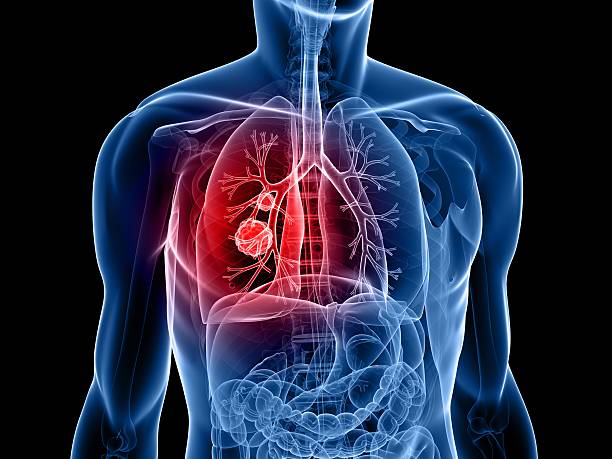

폐암 원인

폐암 원인은 다양하지만 유전적 요인, 환경적 요인, 흡연 등이 있는 것으로 알려져 있으며 가족력이 특히 중요해 가족력이 있는 경우 꾸준한 관리가 중요합니다. 또한, 폐암의 대표적인 병인으로서 흡연은 직간접적인 영향이 강하여 폐암의 병인과 떼려야 뗄 수 없는 중요한 것으로 여겨집니다.